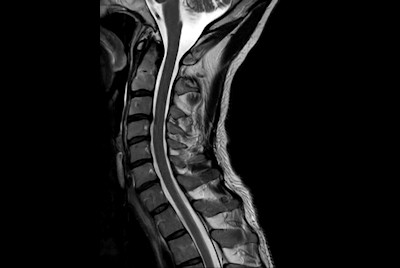

High quality Cervical Spine imaging with SmartSpeed Precise